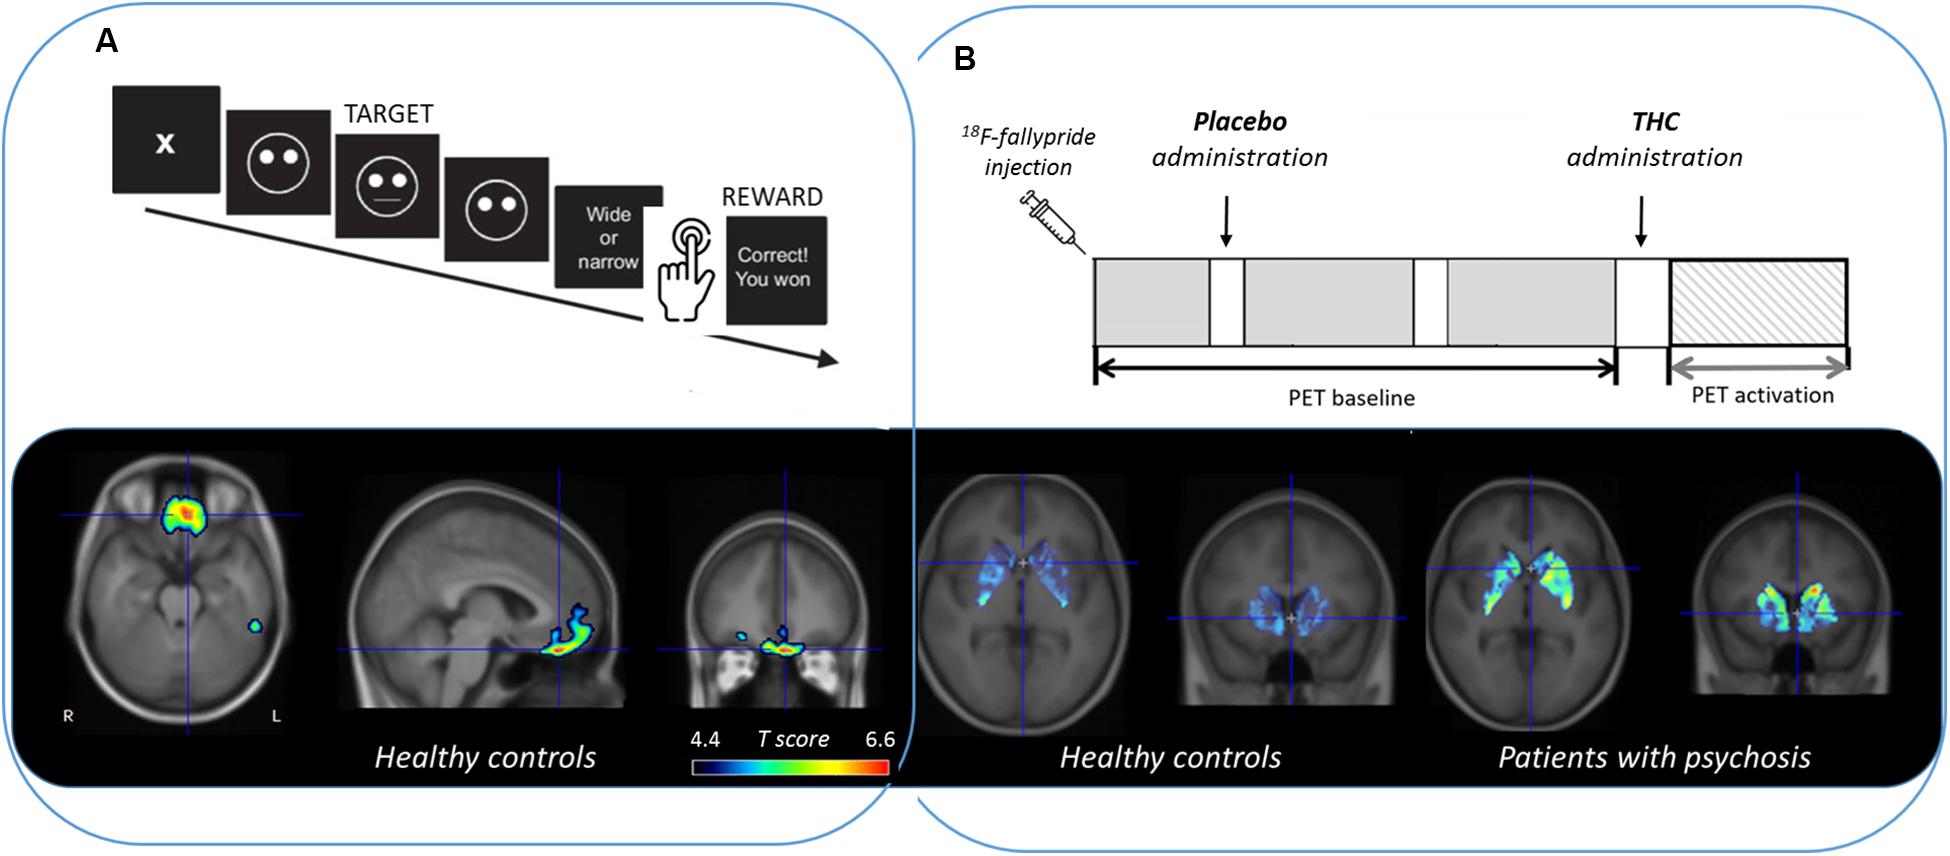

Frontiers Methods for Quantifying Neurotransmitter Dynamics in the Living Brain With PET Imaging